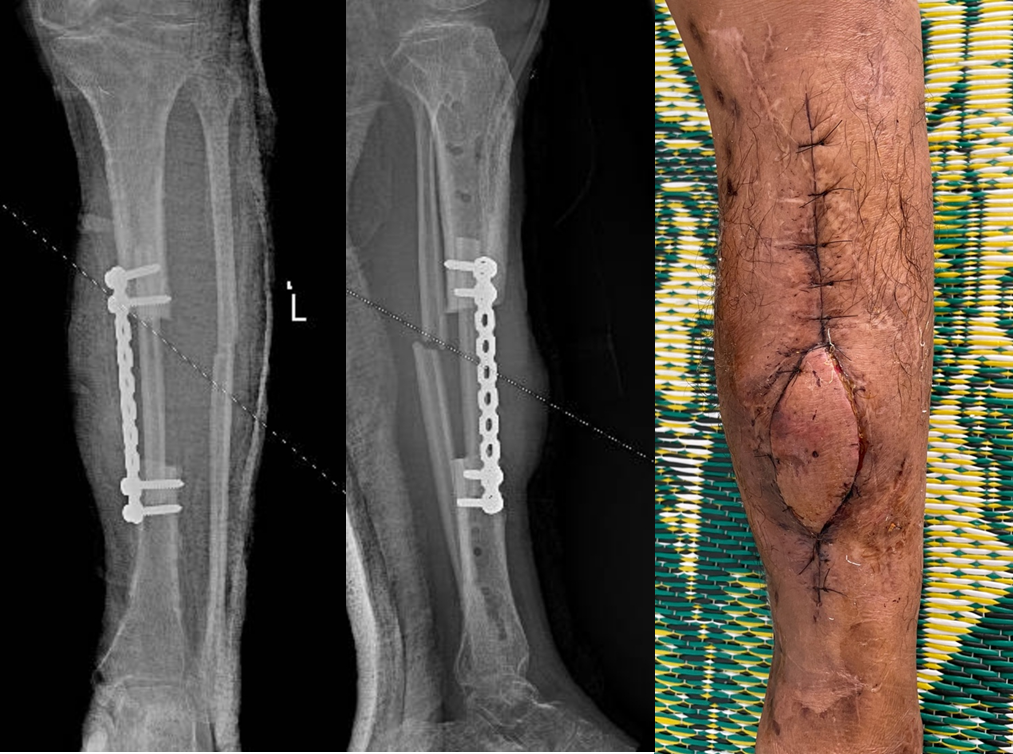

Đoạn xương mác dài 12cm kèm cuống mạch

Hình XQ xương sau mổ và vạt da sống tốt sau 10 ngày

XQ xương sau mổ và vạt da sống tốt sau 10 ngày